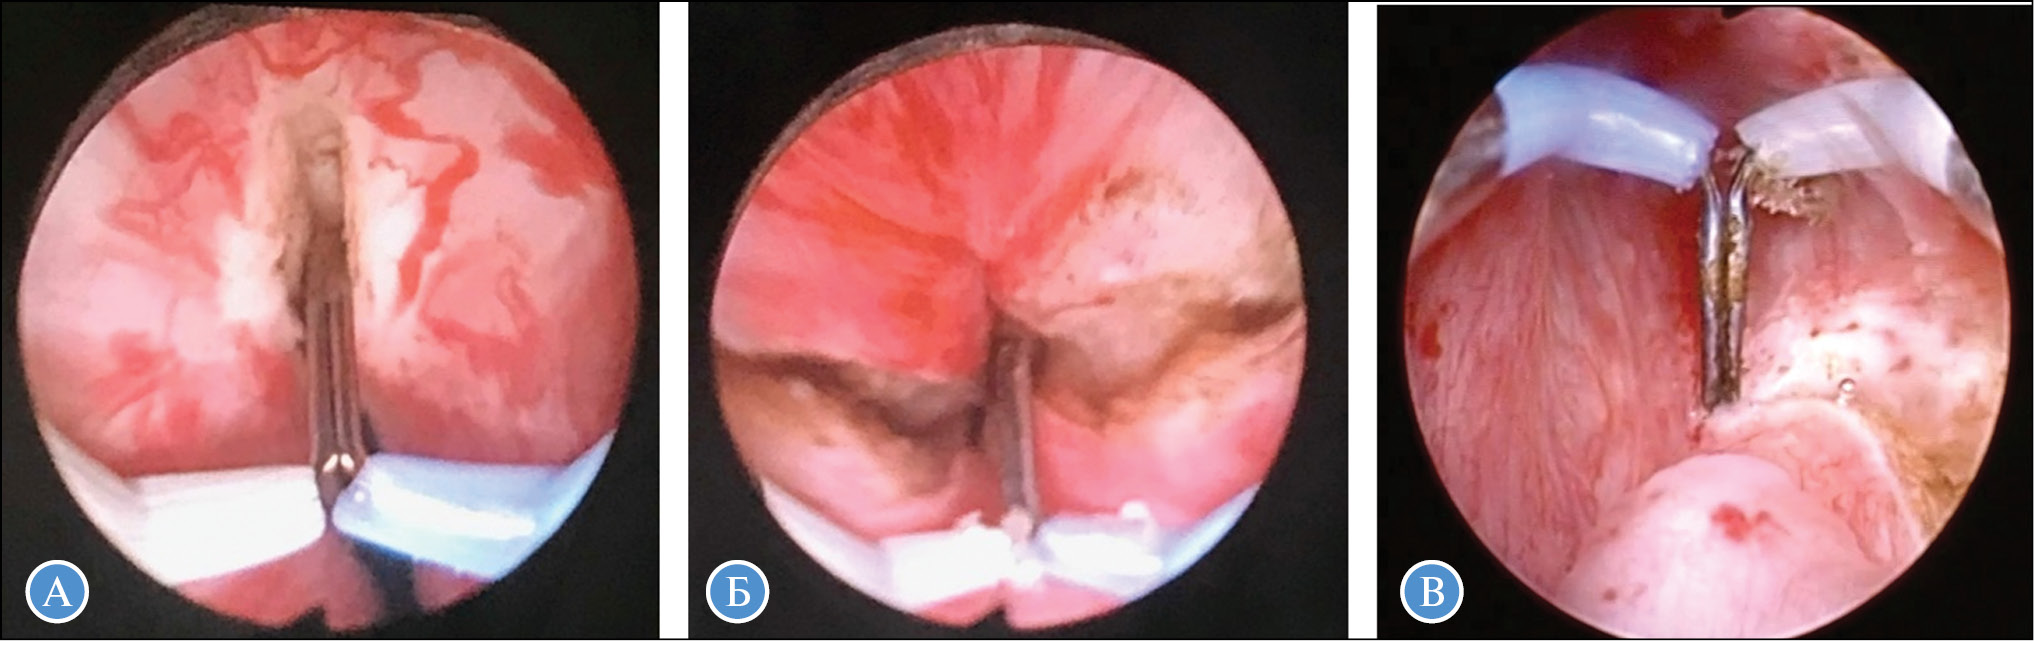

Энуклеация долей ПЖ начинается от обнаженной области хирургической капсулы вокруг семенного бугорка в проксимальном направлении к шейке МП, при наличии средней доли энуклеация начинается с нее. Доли ПЖ отделяют от капсулы при помощи электрода-толкателя Plasma-TUEB-Loop, затем выделенная часть для последующей энуклеации измельчается большой петлей Plasma-Loop, что обычно сопровождается минимальным кровотечением. Следующим этапом энуклеируется оставшаяся часть аденомы с сохранением «мостика» по задней поверхности ПЖ ближе к шейке МП для предотвращения миграции простаты в просвет МП. Далее после замены электрода на стандартный Plasma-Loop начинают послойную резекцию вылущенных долей железы (рис. 2).

Рис. 2. Основные этапы плазменной трансуретральной энуклеации простаты при доброкачественной гиперплазии простаты больших и гигантских размеров: А — циркулярное рассечение слизистой в области шейки мочевого пузыря и апикальной части; Б — механическое отделение левой доли железы от капсулы; В — резекция вылущенной доли

После полной резекции долей рассекают тканевый «мостик» без капсулы ПЖ, удаляют все остатки аденомы в верхушке железы, по возможности избегая рассечения сфинктера, чтобы исключить послеоперационное недержание мочи. На заключительном этапе операции резецированные ткани удаляют с помощью морцеллятора или обычной петли Plasma-Loop, устанавливают катетер Фолея в МП обычно на 24–72 ч, как правило, не более 48 ч. Энуклеация ДГП выполняется тем легче, чем больше ее объем.